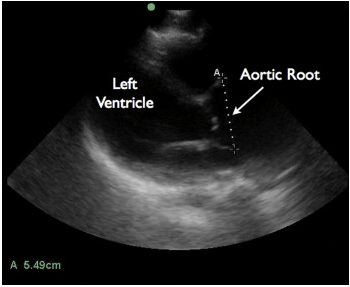

In a recent article in the Journal of Emergency Medicine, Dr. Resa Lewiss and friends, discuss 2 cases of thoracic aortic aneurysm identification by focused cardiac ultrasound. It is a great case report that highlights the need to include the aortic root and descending thoracic aorta in the parasternal long view of your focused cardiac echo.

“A 60-year-old man presented to the emergency department (ED) after a blunt traumatic injury to his back while at work. During the focused cardiac ultrasound examination, the aortic outflow tract distal to the aortic valve appeared enlarged and the aortic root measured 5.49 cm.

Screen Shot 2014-03-04 at 9.16.55 AM

“An 82-year-old man with hypertension presented to the ED with 1 month of chest pain radiating to the back. The focused cardiac ultrasound examination demonstrated enlargement of the descending thoracic aorta at 4.82 cm.”